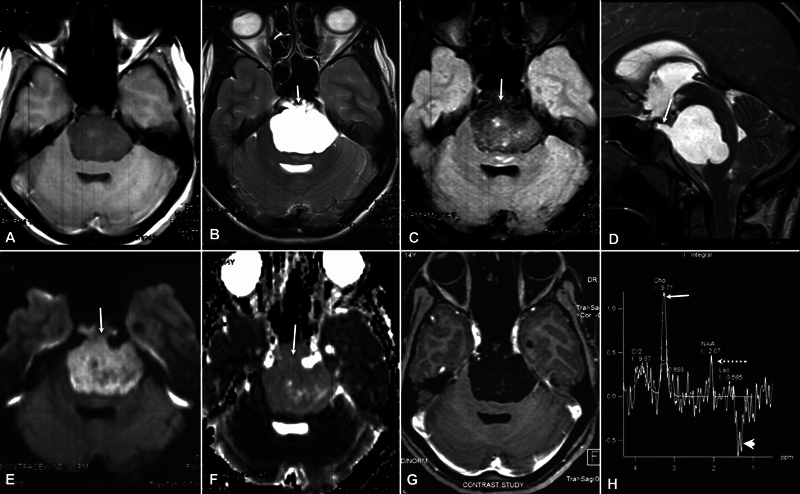

硬膜前脊索瘤是一种极为罕见的肿瘤,与骨内源性脊索瘤相比,它具有良性特征,不会复发,预后良好。放射学上,它可能与表皮样囊肿相似,给影像学带来挑战。在此,我们介绍一例因头痛、肢体和面部无力而就诊的中青春期女孩的病例。在大脑前蝶窦发现了一个不强化、弥散受限、以硬脑膜内囊性包块为主的肿块病变。起初怀疑是表皮样囊肿,但组织病理学检查发现是脊索瘤。蝶窦的破坏很重要,脊索瘤应纳入鉴别诊断。

Intradural prepontine chordoma is an extremely rare entity and depicts benign features with no recurrence and has a good prognosis as compared with bone endogenous chordoma. Radiologically, it may mimic an epidermoid cyst and present an imaging challenge. Here we present a case of a middle adolescent girl who presented with headache along with limb and facial weakness. A nonenhancing, diffusion-restricting, predominantly intradural cystic-appearing mass lesion was seen in the prepontine cistern. Initially, an epidermoid cyst was suspected, but histopathology revealed it to be a chordoma. Destruction of the clivus is important and chordoma should be included in differential diagnosis.